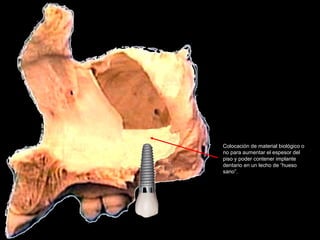

Colocación de material biológico o

no para aumentar el espesor del

piso y poder contener implante

dentario en un lecho de “hueso

sano”.

Uno de los fenómenos fisiológicos más comunes es la falta de hueso en el

Piso del antro de Highmore, secundario a la neumatización de los senos y

Que en muchas ocasiones aproxima el piso antral al proceso alveolar, por

Lo que sobre todo en pacientes jóvenes es factible dar volumen a este

Área con la aplicación de injerto de hueso humano, equino o derivados de

arcillas de sílice. Las indicaciones de usar uno u otros depende de la experiencia

Clínica del operador.